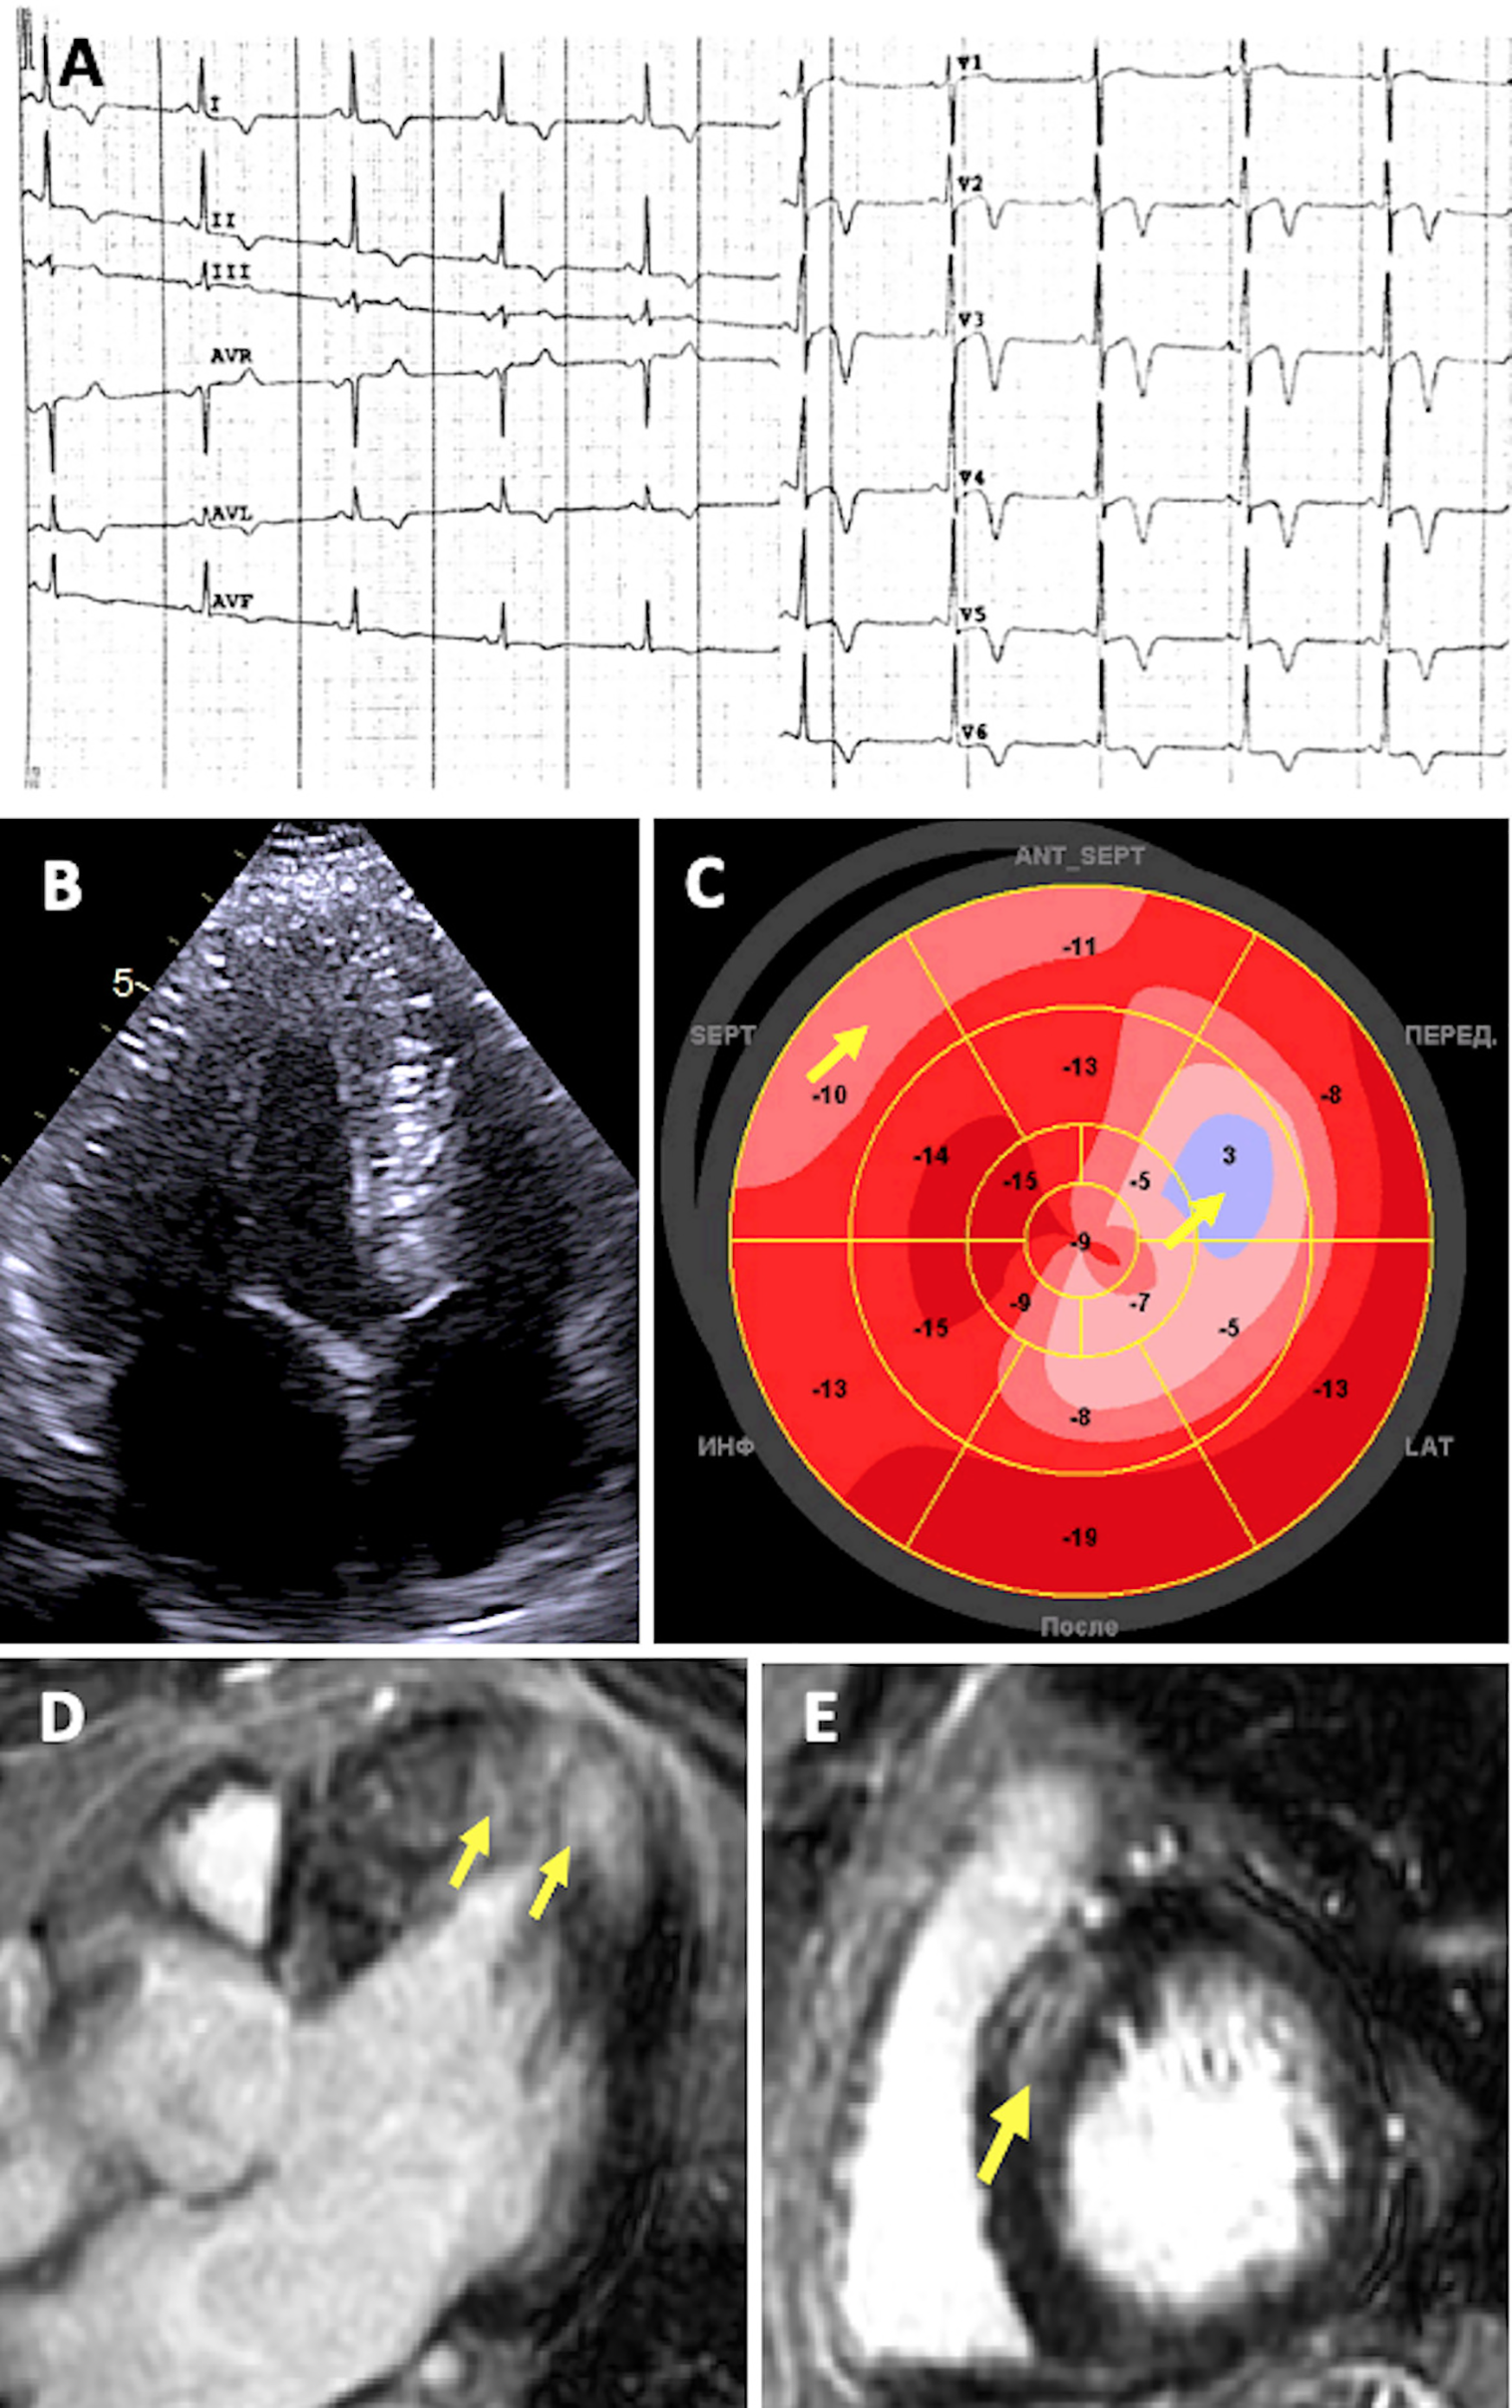

Figure 3

Diagnostic features of patient with desminopathy. (A) ECG showing sinus bradycardia and prominent repolarization abnormalities: ST segment elevation followed by deep T-wave inversions in precordial and standard leads, with a positive T wave in aVR. (B) 2D ECHO apical four-chamber view showing symmetric concentric LV hypertrophy. (C) Decreased global longitudinal strain (“bovine eye” – 11.9%) Arrows indicate more prominent localized abnormalities in systolic deformation. (D–E) CMR imaging showing replacement fibrosis. Arrows indicate LGE located in the same segments with decreased strain.